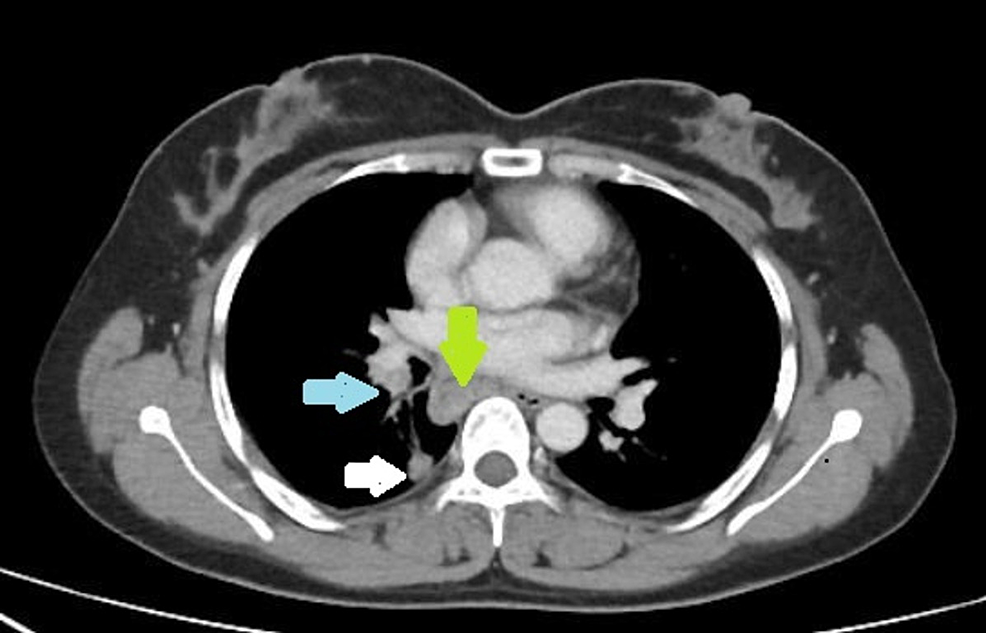

Ct Scan Enlarged Lymph Nodes Can Chest X Ray Detect Enlarged Lymph Nodes These can be cancerous, enlarged lymph nodes,. Cervical lymph node metastasis (radiologic criteria). In general 10 mm is considered the upper limit for. While some cancers such as lung. This test isn’t needed if a ct of the chest is done. There are many causes of enlarged lymph nodes in the chest. Generally, mediastinal lymphadenopathy is diagnosed with imaging tests,. Can Chest X Ray Detect Enlarged Lymph Nodes.

Chest CT scan shows multiple enlarged lymph nodes in the left hilum and Can Chest X Ray Detect Enlarged Lymph Nodes Cervical lymph node metastasis (radiologic criteria). In general 10 mm is considered the upper limit for. The short answer, no, not always. These can be cancerous, enlarged lymph nodes,. This test isn’t needed if a ct of the chest is done. Generally, mediastinal lymphadenopathy is diagnosed with imaging tests, such as chest ultrasound, chest computed tomography (ct), positron emission tomography.. Can Chest X Ray Detect Enlarged Lymph Nodes.

(a) A chest CT shows multiple enlarged lymph nodes in mediastinum. (b Can Chest X Ray Detect Enlarged Lymph Nodes This test isn’t needed if a ct of the chest is done. Generally, mediastinal lymphadenopathy is diagnosed with imaging tests, such as chest ultrasound, chest computed tomography (ct), positron emission tomography. The short answer, no, not always. There are many causes of enlarged lymph nodes in the chest. These can be cancerous, enlarged lymph nodes,. Cervical lymph node metastasis (radiologic. Can Chest X Ray Detect Enlarged Lymph Nodes.

CT chest and thorax showing multiple enlarged mediastinal lymph nodes Can Chest X Ray Detect Enlarged Lymph Nodes While some cancers such as lung. The short answer, no, not always. Cervical lymph node metastasis (radiologic criteria). This test isn’t needed if a ct of the chest is done. Generally, mediastinal lymphadenopathy is diagnosed with imaging tests, such as chest ultrasound, chest computed tomography (ct), positron emission tomography. There are many causes of enlarged lymph nodes in the chest.. Can Chest X Ray Detect Enlarged Lymph Nodes.

The figure shows an axial CT image with window adjusted to display both Can Chest X Ray Detect Enlarged Lymph Nodes Generally, mediastinal lymphadenopathy is diagnosed with imaging tests, such as chest ultrasound, chest computed tomography (ct), positron emission tomography. This test isn’t needed if a ct of the chest is done. In general 10 mm is considered the upper limit for. While some cancers such as lung. The short answer, no, not always. There are many causes of enlarged lymph. Can Chest X Ray Detect Enlarged Lymph Nodes.

Chest computed tomography (CT) (mediastinal window)enlarged mediastinal Can Chest X Ray Detect Enlarged Lymph Nodes Generally, mediastinal lymphadenopathy is diagnosed with imaging tests, such as chest ultrasound, chest computed tomography (ct), positron emission tomography. These can be cancerous, enlarged lymph nodes,. Cervical lymph node metastasis (radiologic criteria). In general 10 mm is considered the upper limit for. This test isn’t needed if a ct of the chest is done. While some cancers such as lung.. Can Chest X Ray Detect Enlarged Lymph Nodes.